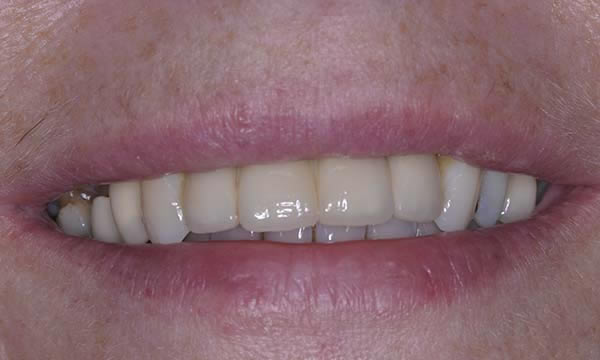

Case E

The delayed immediate protocol was implemented, following extraction of the upper incisor teeth and following 3 months of healing, a temporary bridge was used to ensure occlusal harmony and predictable papillae formation. 15 months later, after a recent review, Mrs Murphy is still very happy, smiling and says they feel and perform just like natural teeth.

After Treatment